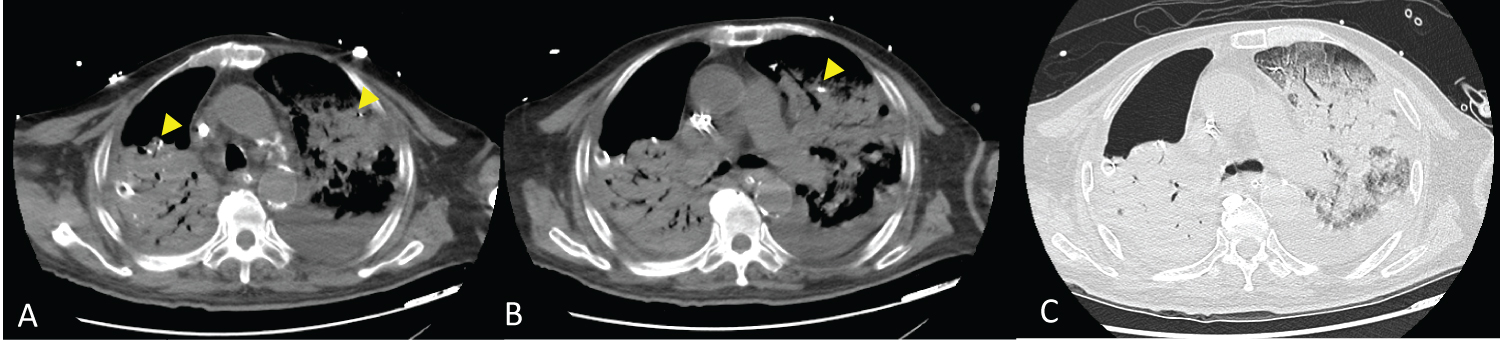

The patient was admitted to the intensive care unit (ICU) postoperatively, and the hemodynamics were stabilized with taper off of the inotropic agent. Thoracolumbar spine computed tomography (CT) was performed on the first postoperative day to check the instrument position. All of the implants were in a good position, but a small amount of cement leakage was suspected over the left side segmental artery of L3 (Figure 2).

Figure 2: Postoperative lumbar spine computed tomography.

High attenuation bone cement (arrow) was noted over the left side segmental artery of L3 in postoperative computed tomography (A), which was not seen on preoperative computed tomography (B). View Figure 2